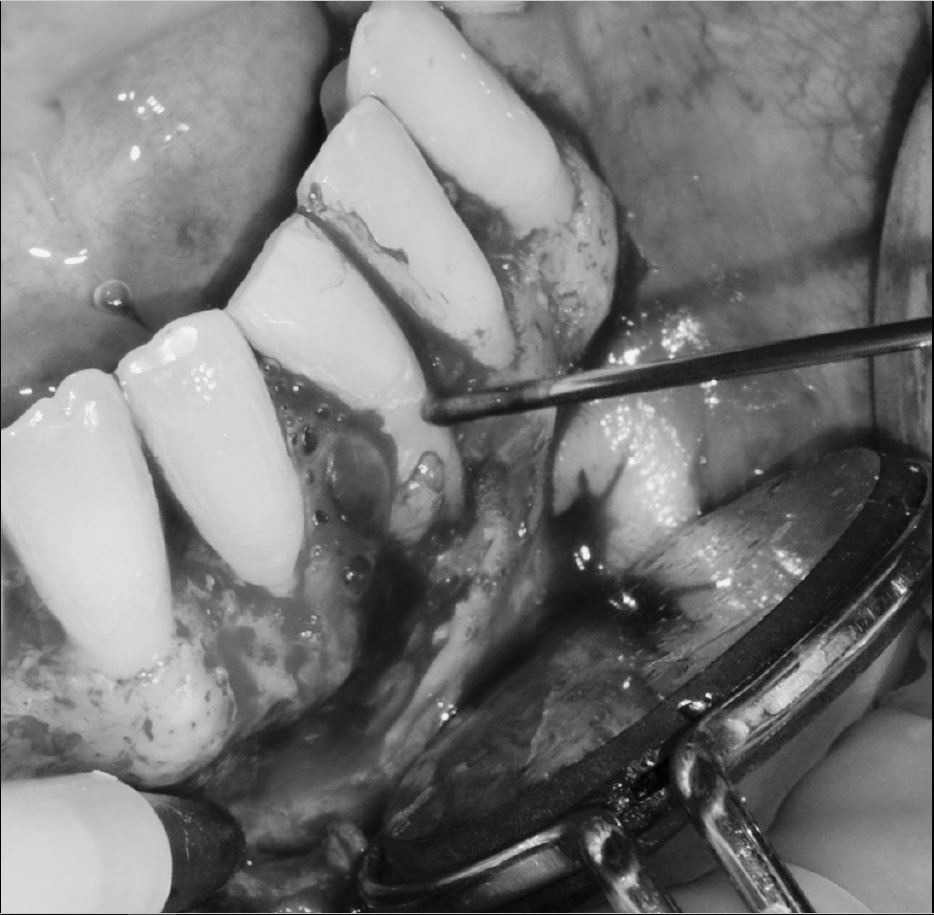

Aplicación protocolo emdogain

Regeneración ósea guiada con membrana de colageno creos de Nobel Biocare y relleno óseo mediante BIOSS Collagene de INIBSA, con elementos de fijación a la membrana para R.O.G.

Fotografías del proceso: